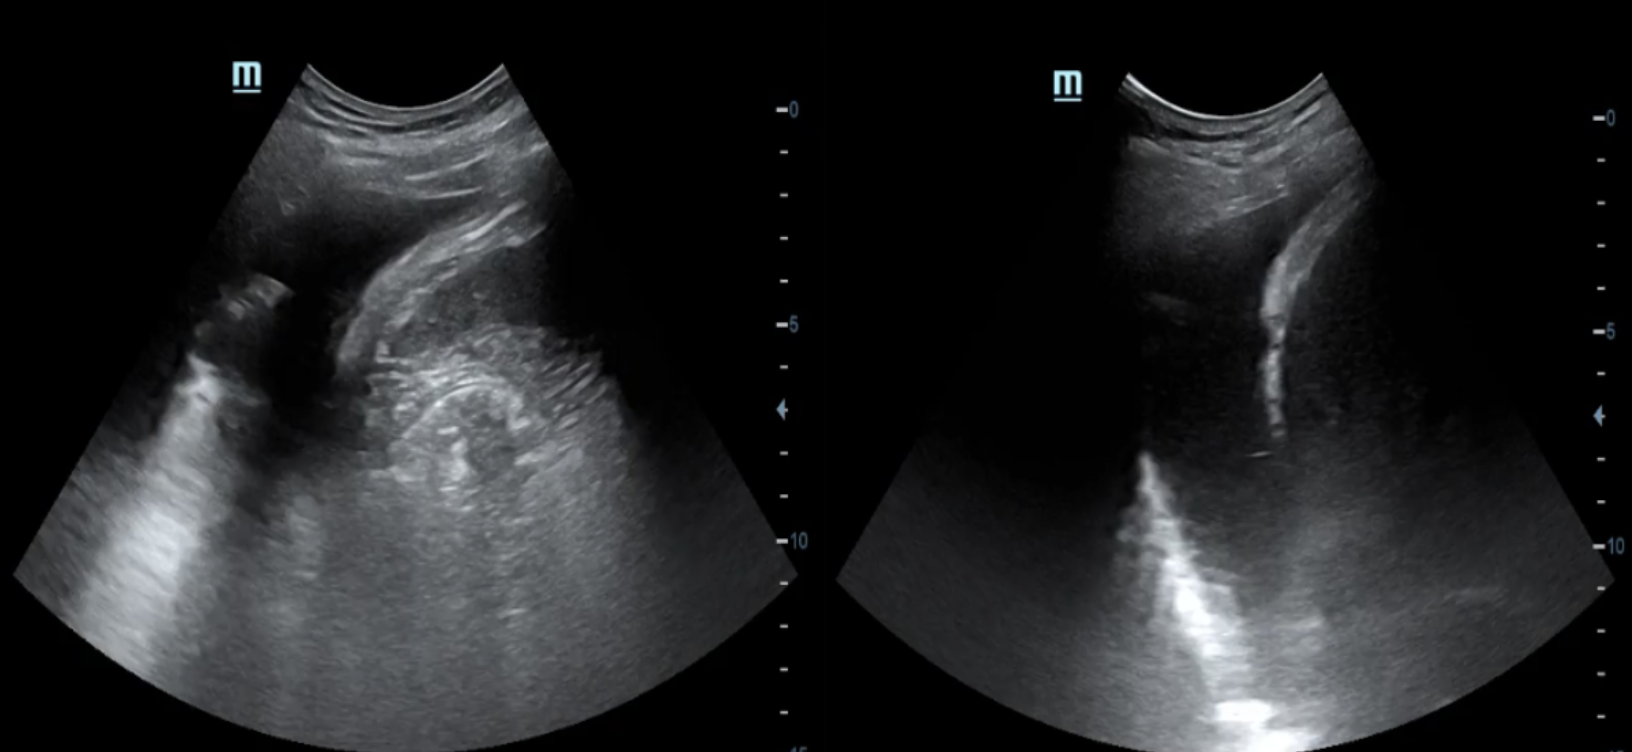

A la exploración ecográfica pulmonar se objetivan líneas B en ambos campos anteriores y superiores, así como derrame pleural bilateral, orientando la causa de la disnea hacia la insuficiencia cardíaca.

A nivel cardiológico, observamos una disminución de la fracción de eyección y un aumento de la presión venosa central.

De esta manera se descartan otras causas de disnea como la neumonía o TEP, y se confirma la insuficiencia cardíaca.